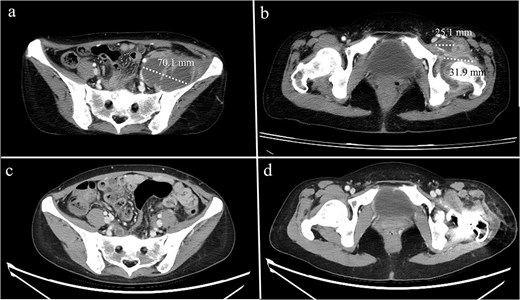

A 44-year-old female, with a medical history of invasive ductal carcinoma of the breast with multiple sites of metastasis (brain, pulmonary, liver, and bone), presented to the outpatient clinic with progressive intractable pain over the left inguinal area in the preceding month. Radiography revealed symmetrical joint space narrowing of the left hip joint (Fig. 1). Computed tomography (CT)revealed a well-lobulated cystic lesion within the left psoas muscle, extending caudally into the hip joint (Fig. 2a and b). The serum C-reactive protein (CRP) level was 55.04 mg/dl at admission. Due to the inaccessibility of CT-guided percutaneous abscess drainage, she underwent a scheduled surgical debridement of the psoas abscess. Resection arthroplasty with polymethylmethacrylate hip spacer implantation was planned simultaneously.

Computed tomography of a 44-year-old female demonstrating (a) a psoas abscess and (b) hip septic arthritis. Postdebridement surgery and resection arthroplasty, the abscess completely resolved (c, d).

A bacterial culture of the pus yielded Staphylococcus aureus. After debridement surgery and parental use of sensitive antimicrobial agents, the CRP levels decreased over time (Fig. 4). A repeat CT scan revealed a completely diminished abscess within the iliac fossa (Fig. 3c and d). The patient underwent total hip arthroplasty three months after the first surgery. However, she died 2 months later because of multiple organ failure caused by cancer metastasis.